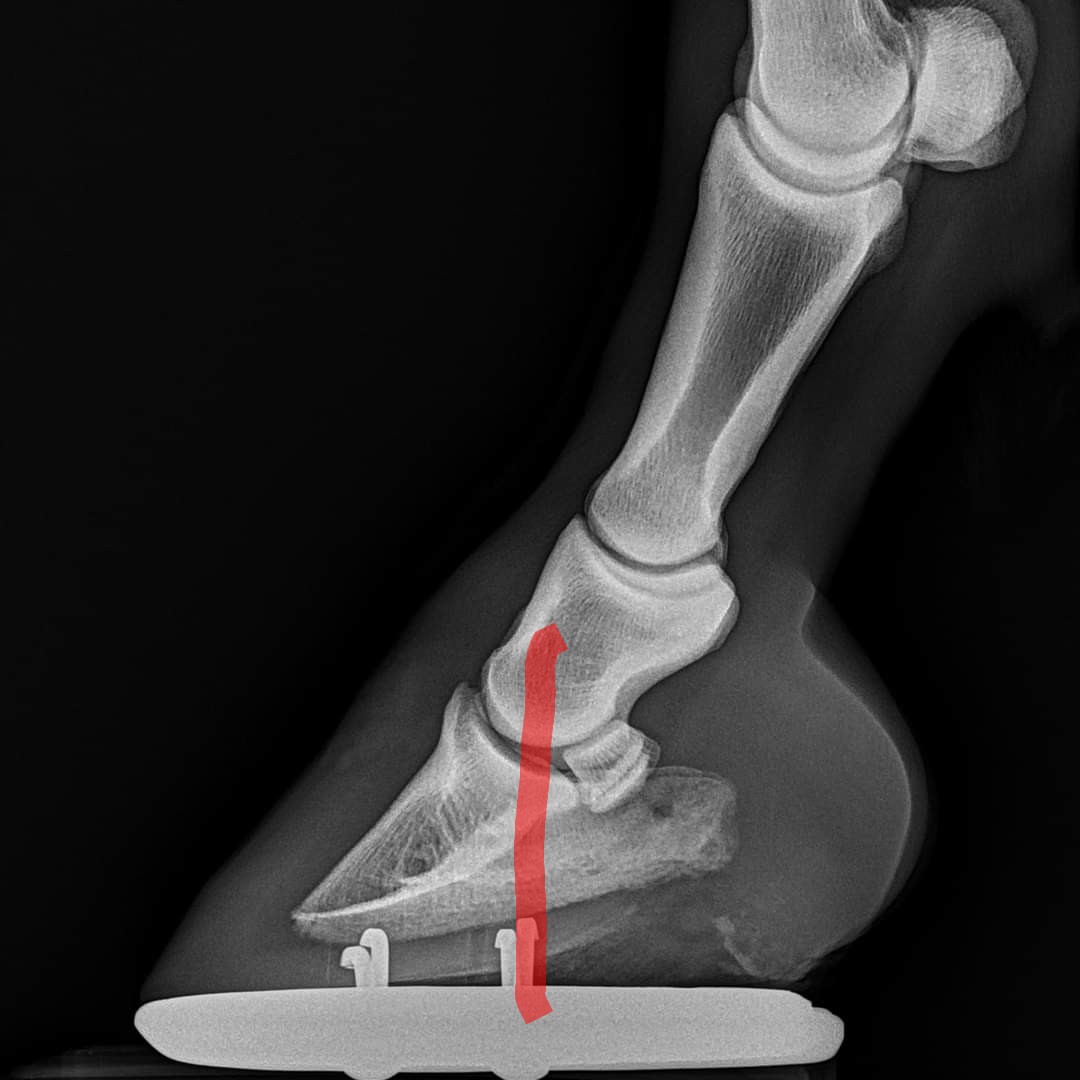

Tyvärr medför en anatomiskt för hög häl att hovbenet inne i hovkapseln även det höjs i bakkant och tippar… framåt.

Trycket på hovbenet i tån blir då för högt och kraften som hästen trycker ner på hovleden blir fel och med tiden uppstår ofta hälta.